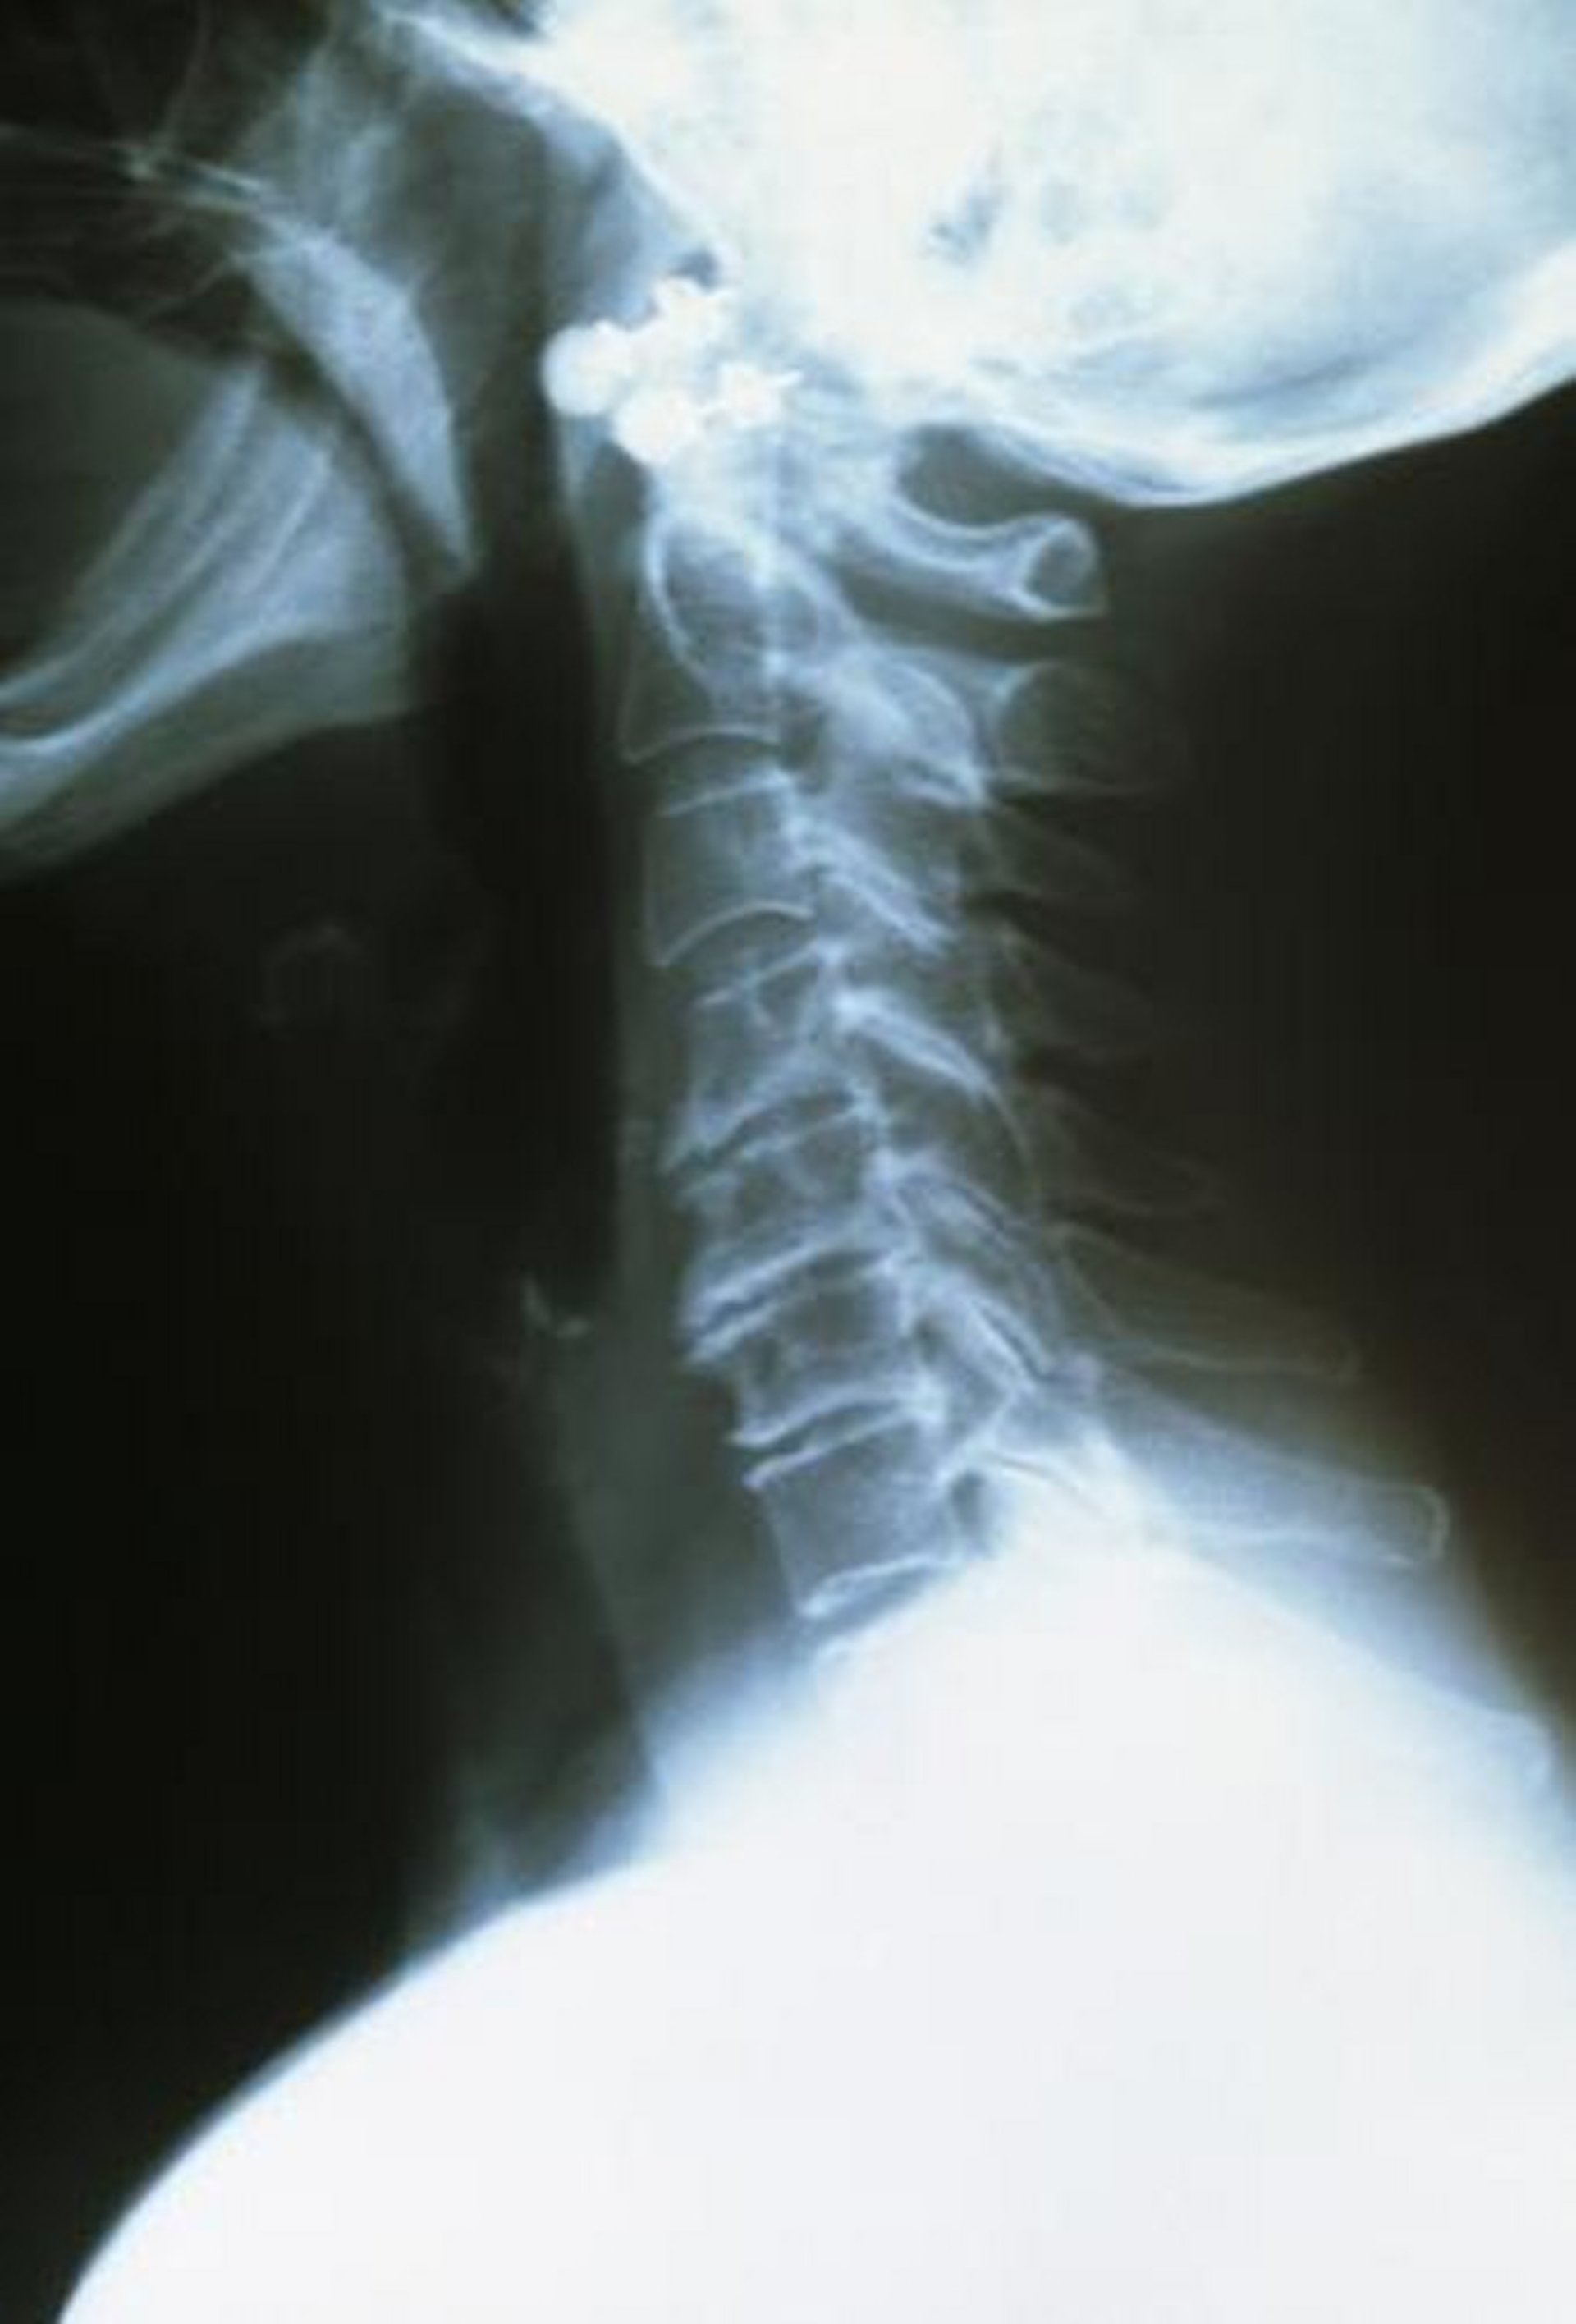

Cervical Osteoarthritis

The upper cervical vertebrae are healthy, well spaced, and smooth edged. The arthritic lower vertebrae are closer together and have rough and ragged edges.